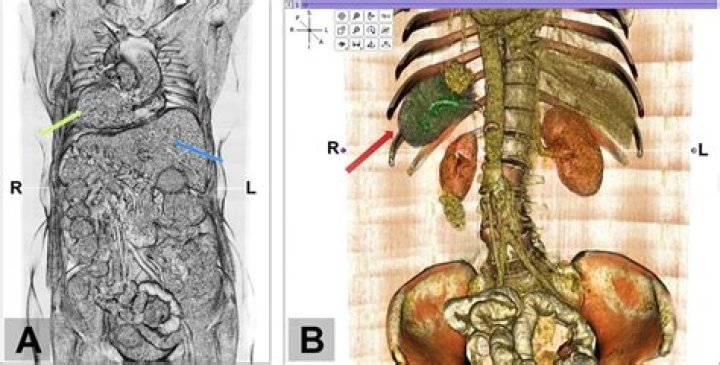

Situs inversus is a rare congenital condition in which all of an individual’s internal organs in the thorax and abdomen are positioned on the opposite side to where they should be. The liver, for instance, is now on the left, the spleen on the right. Flipped, for want of a better word.

Situs describes the position of the cardiac atria and viscera. Situs solitus is the normal position, and situs inversus is the mirror image of situs solitus (see the image below). Cardiac situs is determined by the atrial location.